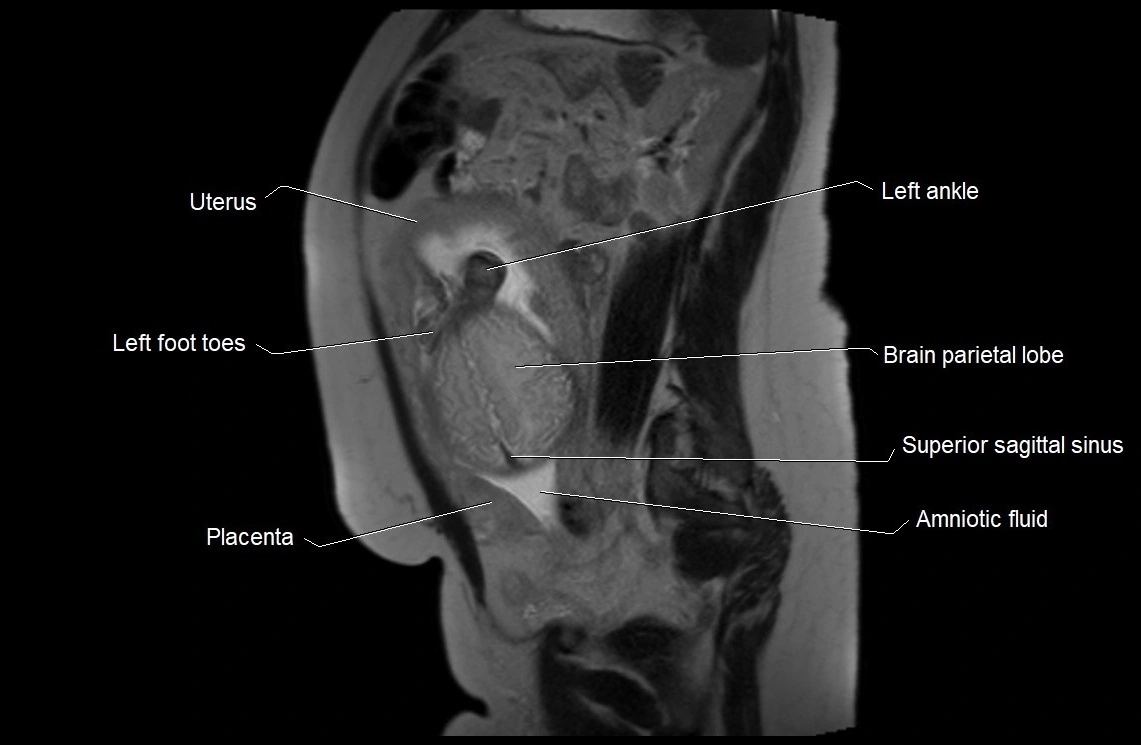

MRI Appearance

T2 HASTE (T2 GRE):

• Amniotic fluid shows very bright hyperintense signal

• Provides natural contrast against fetus and placenta

• Small particles (vernix) may appear as scattered hypointense foci within bright fluid

MRI image

image